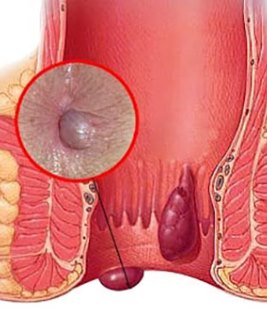

HEMORROIDES